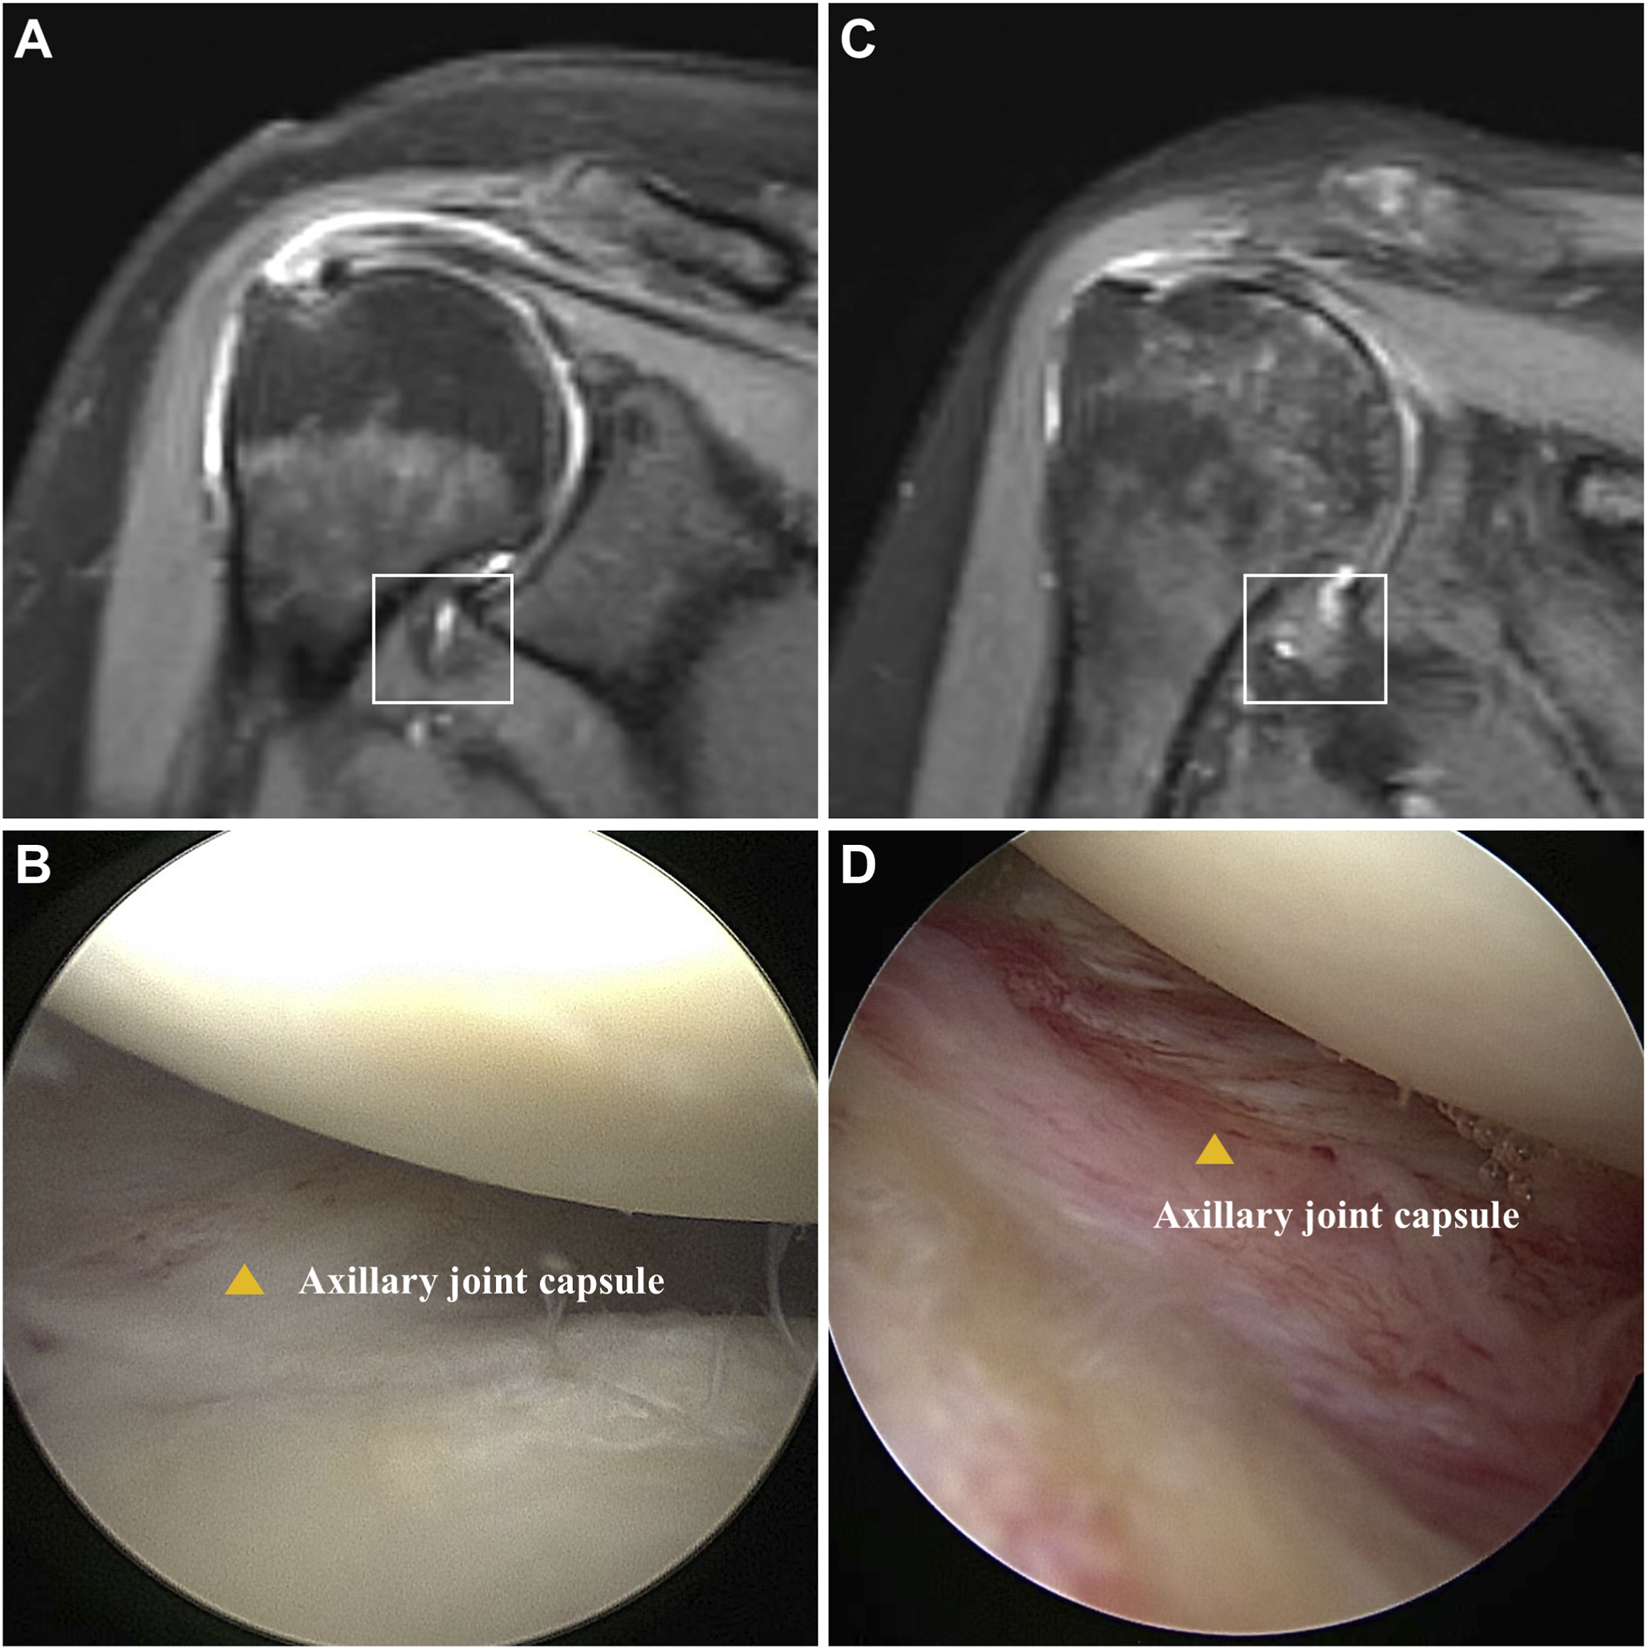

A total of 12 patients (6 for SS and 6 for non-SS) were included in this study, and the shoulder joint capsules were collected. The baseline data and ROM measurement results were demonstrated in Table 1. There was no significant difference in gender, age, BMI, or symptom duration between SS and non-SS groups. However, a significantly decrease of ROM was observed in SS patients, indicating joint stiffness. Additionally, there were higher VAS scores and lower Constant scores in the SS group, reflecting severe pain and functional impairment. MRI results showed significant thickening and edema in the capsule of SS patients (Figures 1A,C). Pronounced capsule hyperplasia and swelling were observed in the SS group under arthroscopy (Figures 1B,D). These results suggested that there were significant joint stiffness, capsule fibrosis and function impairment in SS patients.

FIGURE 1

Comparison of patients with and without SS. (A) Oblique coronal fat-suppressed T2-weighted MRI shows no thickening or edema of the humeral joint capsule in the axillary recess (square). (B) Arthroscopy revealed no hyperplasia or redness and swelling in the axillary joint capsule (yellow triangle). (C) Oblique coronal fat-suppressed T2-weighted MR image showed thickening and edema of joint of axillary recess (square). (D) Arthroscopy revealed hyperplasia and redness of the axillary capsule of the shoulder joint (yellow triangle).